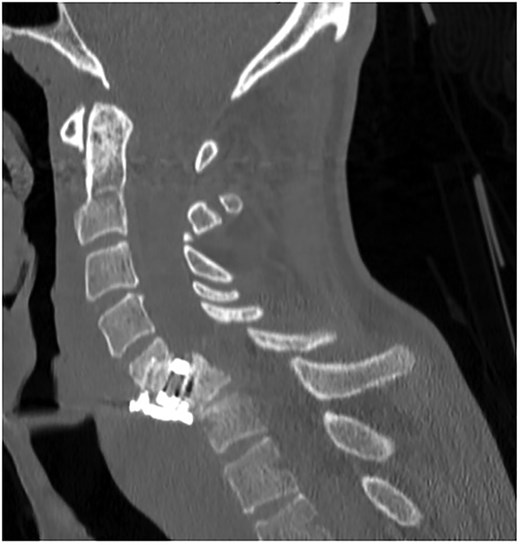

A 35-year-old male presented with a month-long history of dysphagia, severe headache, and posterior neck pain that radiated to the occiput. His medical history was significant for cervical surgeries, including an anterior cervical discectomy and fusion (ACDF) at C5/C6 one year and two months ago (Fig. 1). Shortly thereafter, the patient underwent revision surgery along with posterior plating from C5 to T1 due to osteomyelitis, worsening cervical deformity, and retropharyngeal abscess (Fig. 2). Initial workup included a noncontract computed tomography (CT), demonstrating increased gas density at C6 corpectomy site and post cricoid region (Fig. 3). A swallow study was obtained based on suspicion of a perforation and demonstrated extraluminal leakage of contrast posteriorly at the C6 level, consistent with initial CT (Fig. 4). Surgery included removal of the anterior and posterior hardware and esophageal repair. Although initially the esophageal injury was suspected to be related to the hardware, intraoperatively, it was found the instrumentation was not in communication with the esophagus. This confirmed the perforation was unrelated to direct injury from the cervical hardware construct, which was intact. The esophagus was repaired with a pectoralis flap. The postoperative course was uneventful, and the patient was discharged home after one week. The patient later died due to severe complications of substance abuse unrelated to the operation.

Sagittal CT of initial ACDF at cervical spine C5/C6 level over one year prior to esophageal perforation.